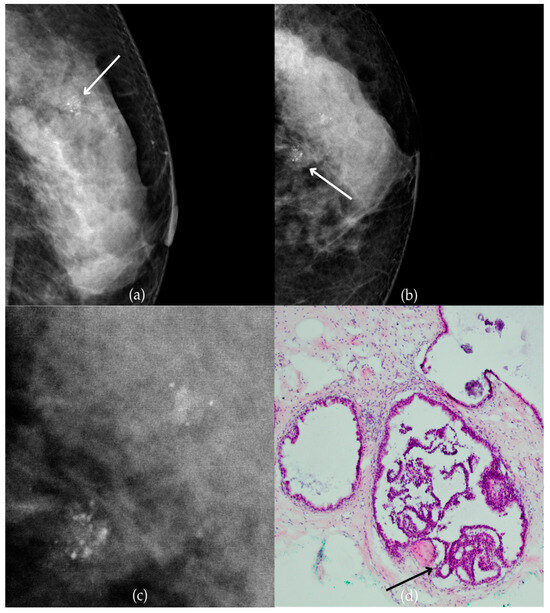

Mammogram and histopathological images (Figure 10) of a 66-year-old patient’s right breast show architectural distortion with associated fine pleomorphic calcifications of segmental distribution in the upper outer quadrant, corresponding to a BI-RADS 3 finding. Tissue analysis obtained through biopsy reported an intraductal papillary lesion without epithelial atypia (category B3). The patient underwent an excisional biopsy (quadrantectomy), and postoperative pathology confirmed the absence of carcinoma. One year after the initial diagnosis, the most recent US follow-up was classified as BI-RADS 2, confirming benign findings.

Figure 10.

Intraductal papillary lesion without epithelial atypia. (a) Mediolateral oblique (MLO) view; (b) craniocaudal (CC) view of the right breast showing architectural distortion with associated fine pleomorphic calcifications of segmental distribution (marked with arrows) in the upper outer quadrant. (c) Magnified mammographic image of fine pleomorphic calcifications of segmental distribution. (d) The histopathological image of the biopsy sample shows an intraductal papillary lesion without epithelial atypia (HE staining; 40× magnification).